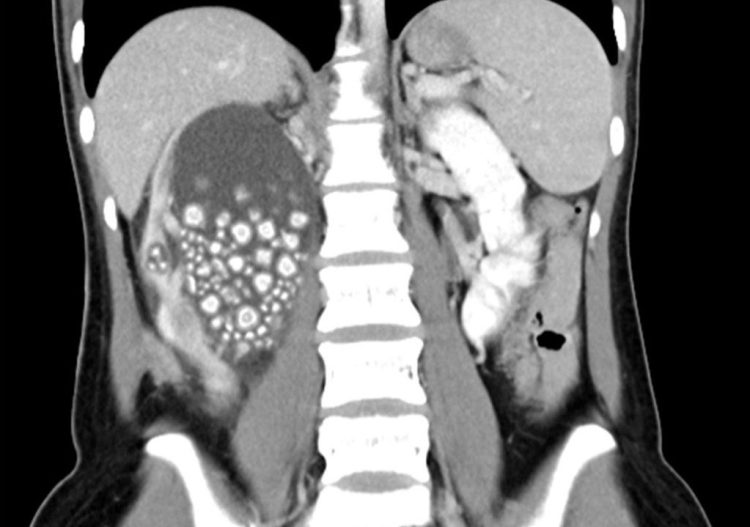

Η 20χρονη εισήχθη σε νοσοκομείο της πόλης Taina, αφού παραπονέθηκε για έντονο πόνο στο κάτω μέρος της πλάτης της. Είχε επίσης πυρετό και μια εξέταση αίματος έδειξε ασυνήθιστα υψηλό αριθμό λευκών αιμοσφαιρίων. Οι γιατροί διέταξαν αξονική τομογραφία η οποία έδειξε ότι το δεξί νεφρό της Yu γεμάτο πέτρες. Αν και πρώτη ενέργειά τους ήταν να χορηγηθούν στη νεαρή γυναίκα αντιβιοτικά, στη συνέχεια προχώρησαν στην αφαίρεση των εκατοντάδων λίθων.

Στο τέλος, οι γιατροί κατέληξαν να αφαιρέσουν πάνω από 300 πέτρες, μεγέθους μεταξύ 5 και 2 εκατοστών. Η ασθενής τους ενημέρωσε ότι δεν έπινε σχεδόν καθόλου νερό και προτιμούσε τα ζαχαρούχα τσάγια και χυμούς για ενυδάτωση. Αυτό της προκάλεσε χρόνια αφυδάτωση.